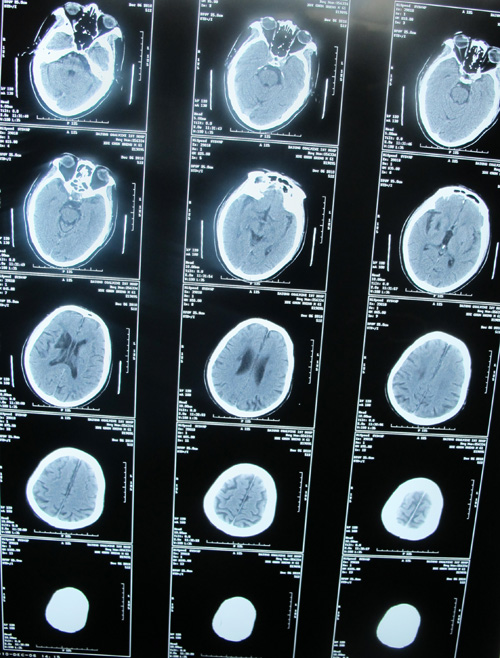

头颈CTA示:右侧颈内动脉近端闭塞,左侧颈总动脉远端及颈内动脉近端重度狭窄

颈部血管超声示:双侧颈动脉粥样斑块形成伴左侧颈动脉狭窄(重度)。

脑梗塞(双侧基底节区)

该患者为急性起病,既往脑梗塞病史13年,心肌梗塞病史1年。右侧颈内动脉近端闭塞,左侧颈总动脉远端及颈内动脉近端重度狭窄,均达到手术指征。患者无明确手术禁忌症,故采取手术治疗,去除病变,改善症状并预防中风发作。